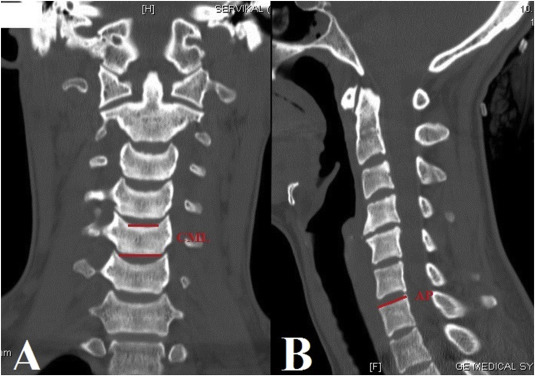

The following parameters were measured on CT scans1 (Fig. 1 ): center mediolateral (CML) diameter of the superior and inferior endplates of C3 to C7 in coronal CT scans2 ; and anterior-posterior (AP) diameter of the superior and inferior endplates of C3 to C7 in sagittal CT scans. Uncinate process and degenerative changes at the lateral border of the vertebrae were excluded in all measurements. Footprints of the most popular CTDPs used in Turkey were compared with anatomic parameters. Data were analyzed using Excel software (Excel 2013, Microsoft, Redmond, WA, USA).

Fig. 1

Fig. 1.

(A) The center mediolateral (CML) diameter of the superior and inferior endplates of C3–C7 in the coronal CT scans. (B) The anterior-posterior (AP) diameter of the superior and inferior endplates of C3–C7 in the sagittal CT scans.